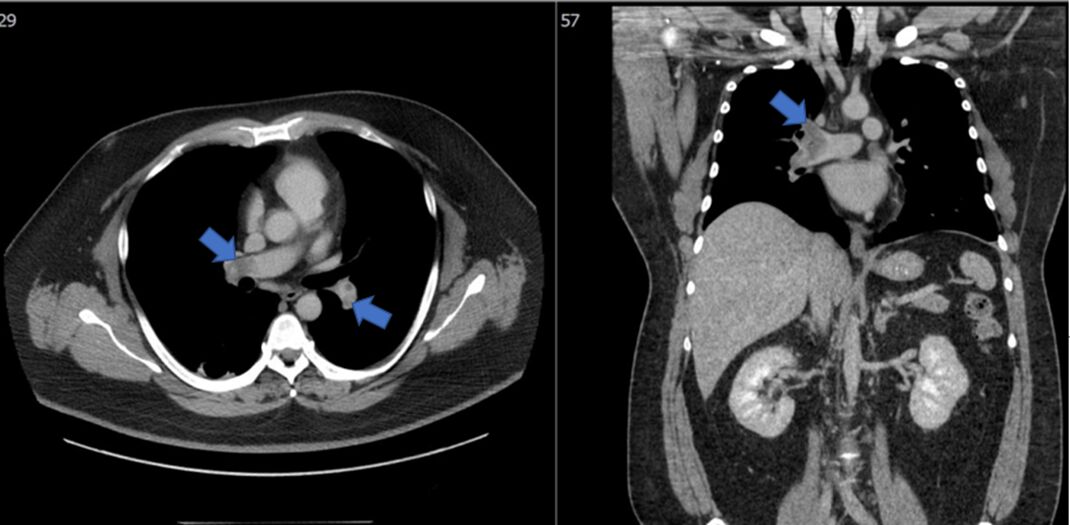

16. 一位55歲女性病患因端坐呼吸與動喘一週而來住院。身體診察發現血壓90/56毫米汞柱,心跳每分 鐘102下,頸靜脈怒張,心音低遠併第三心音,肺部有囉音,雙下肢小腿與腳部水腫。心電圖如圖一。心臟超音波呈現左心室擴大,瀰漫性左心室收縮功能異常,左心室射出分率(left ventricle ejection fraction)為25%。心臟磁振造影檢查如圖二A與B。經食道心臟超音波如圖二C與D。請問下列敘述何者錯誤?

(1)該病患的心電圖呈現 low voltage in frontal leads (2)該病患心電圖呈現心房顫動 (3)該病患之心臟磁 振造影影像檢查呈現左心室心肌緻密化不全(left ventricular non-compaction) (4)該病患之心臟磁振造影影 像檢查呈現急性心肌發炎 (5)該病患應使用口服抗凝血劑 (6)這種疾病有時是因肌節(sarcomere)基因異常 引起 (A) (1)+(3)+(6)。 (B) (2)+(3)+(5)。 (C) (2)+(4)。 (D) (2)+(4)+(5)。